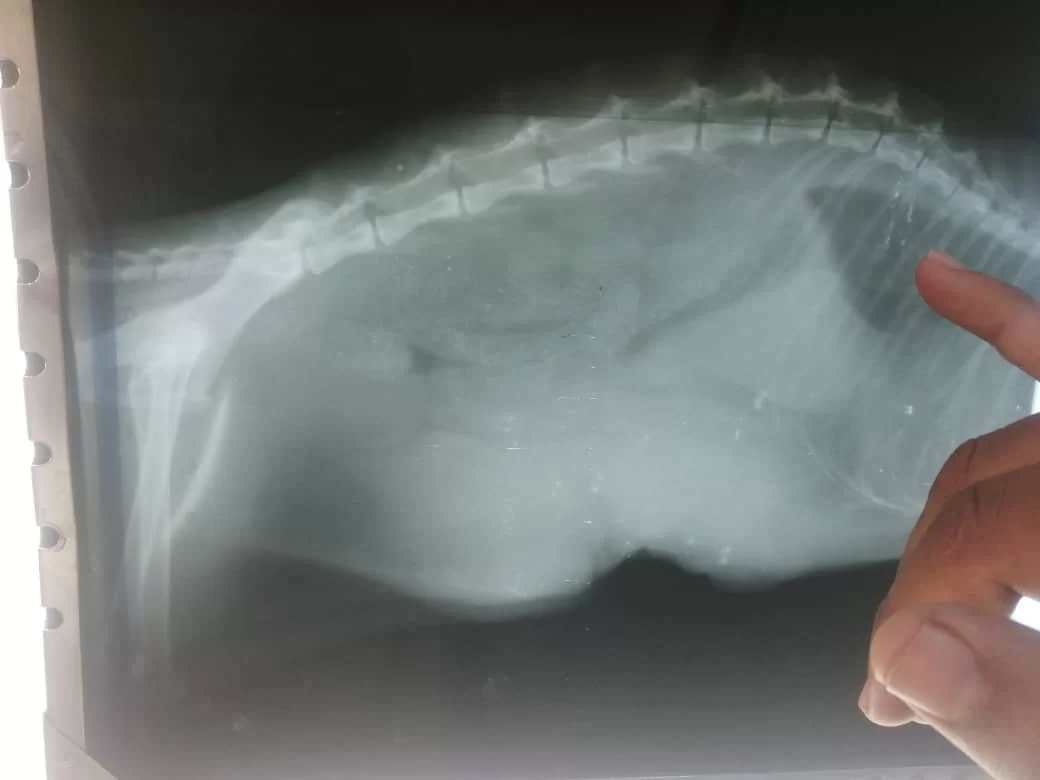

قطة مسنة تعاني من الهزال الشديد، فقدان الوزن والشهية. بعد اخد بيانات الحالة والكشف الاكلينيكي اتضح انها تعاني من وجود تورمات صلبة بمنطقة البطن " اشتباه أورام سرطانية بالغدد اللبنية" وقد تم استئصالها مرتان من قبل.

بإجراء الكشف الاكلينيكي والاشعة السينية التشخيصية اتفق على اخد عينة باثولوجية من الأورام للتأكد من التشخيص المبدئي قبل إجراء أي تدخل جراحي.